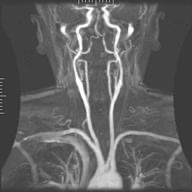

MR angiography (MRA)[edit | edit source]

The displayed parameter in the MRI can be, in addition to the core density and relaxation times T1 and T2, also the flow of excited nuclei. Nucleus movement is then used by MR angiography (MRA), a method showing the flow of blood through blood vessels or the flow of cerebrospinal fluid. To display the flow of nuclei in MR angiography it is possible to use :

MRA using contrast agents

- CE MRA (Contrast Enhanced)

MRA without contrast agents

- TOF MRA (Time of Flight)

- PC MRA (Phase Contrast)

- MRA using contrast agents

The CE MRA technique uses contrast agents to visualize the flow of nuclei. The method can distinguish the arterial phase (filling the arteries with blood) from the venous phase (filling the veins with blood). First, a comparative image is taken without contrast, then an image at the moment when the contrast agent is present in the arteries and finally image is taken after the transfer of contrast agent into the venous system. The MRA image is calculated as the difference between the non-contrast image and the contrast images in the arteries / veins. Contrast agents based on metal compounds are used.

Contrast-free MRA methods are based on changes in the phase of the precessional motion of particles and the size of the magnetization vector in the presence of a gradient magnetic field. The phase change ΔΦ precession is proportional to the velocity of the particles in, the square of the duration tG of the gradient field and the size of the gradient field G:

ΔΦ=vt2G

Phase changes in the MRA image are then manifested either by a loss of signal (decrease in brightness) or a gain in signal (increase in brightness). They therefore manifest themselves similarly to contrast agents. Signal loss is used by the PC MRA (Phase Contrast) method, signal gain is used by the TOF MRA (Time Of Flight) method.

Phase Contrast MRA[edit | edit source]

If the excited area is excited by an RF pulse, then the excited particles of stationary tissues provide a strong signal upon detection. However, the excited blood flow particles leave the scanned scene before the signal is recorded and do not appear in the image. Signal loss is typical only for high flow rates, no signal loss at low speeds. However, the disappearance of the signal can also occur during the phasing out of the precessional motion of the particles, eg during turbulent flow (opposite phases cancel each other out), which occurs at high flow velocities. The resulting MRA image is calculated from the differences between the images taken before and after the application of the magnetic gradient.